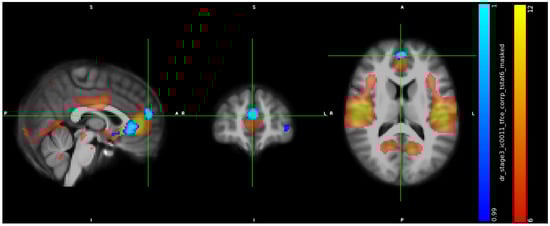

3.2. IC Analysis and Dual Regression

3.3. Neuropsychological Data

3.4. ICA, Neuropsychological Data, and Hormones